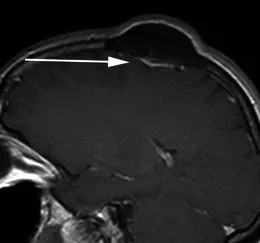

一名49岁女性患者,因头皮肿块就诊。其矢状位增强后T1加权序列显示,左侧顶骨可见一明显骨质增生灶,病灶主体向颅外突出。紧邻骨性病变下方,可见一薄片状、均匀强化的轴外软组织影(箭头所示),符合扁平型脑膜瘤的影像学特征,后经手术病理证实。